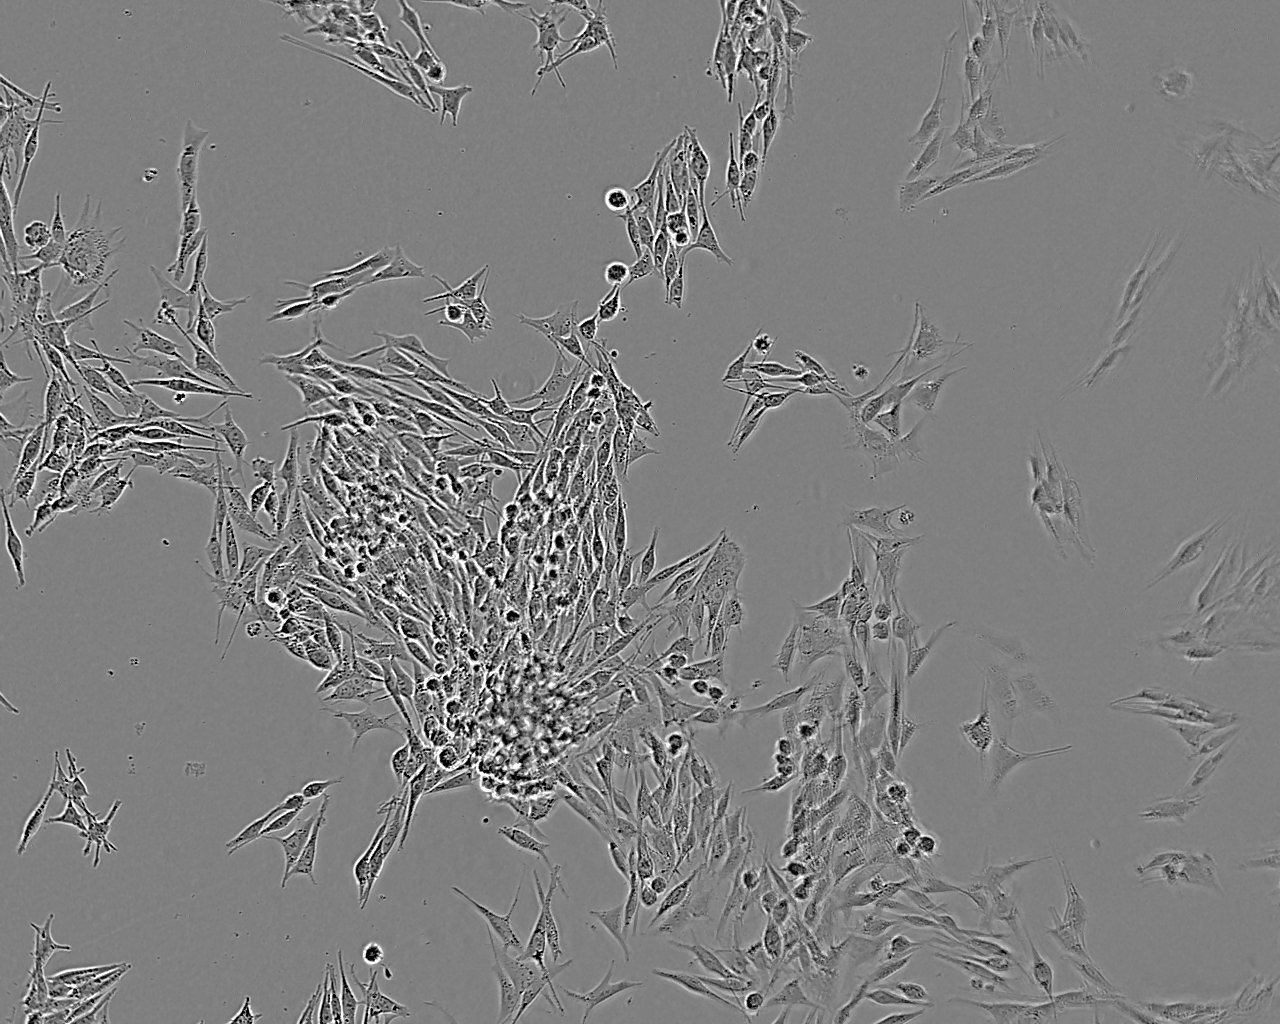

特征特性 从一例原位脉络膜黑色素瘤病例中分离建系。该细胞是ESTDAB计划中收集的超过170株黑色素瘤细胞中的一株

形态特征 上皮细胞样

生长特征 贴壁